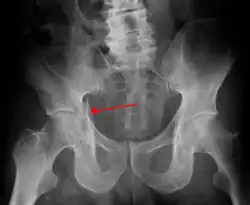

Acetabular fracture as seen on plain X-ray

Fractures of the acetabulum occur when the head of the femur is driven into the pelvis. This injury is caused by a blow to either the side or front of the knee and often occurs as a dashboard injury accompanied by a fracture of the femur.[1]